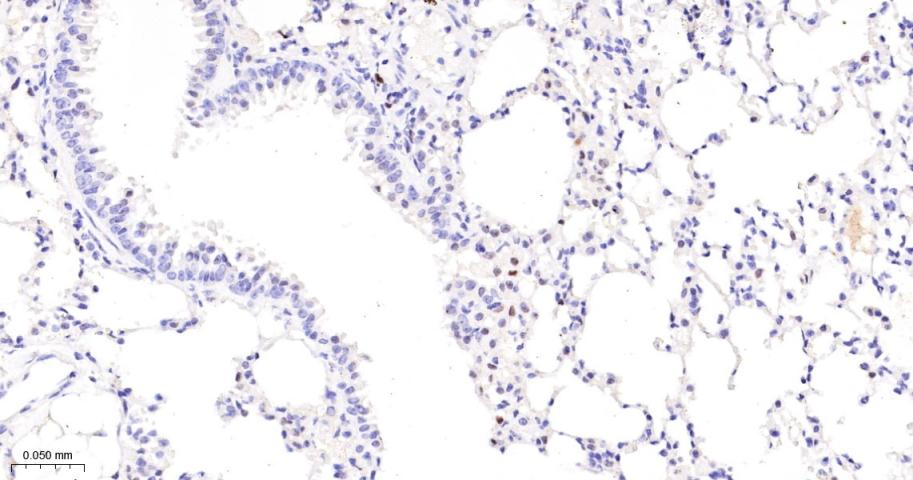

Paraformaldehyde-fixed, paraffin embedded Mouse Lung; Antigen retrieval by boiling in sodium citrate buffer (pH6.0) for 15 min; The section was incubated with JUNB Monoclonal Antibody, Unconjugated (bsm-60454R) at 1:200 overnight at 4°C, followed by conjugation to the bs-0295G-HRP and DAB (C-0010) staining.